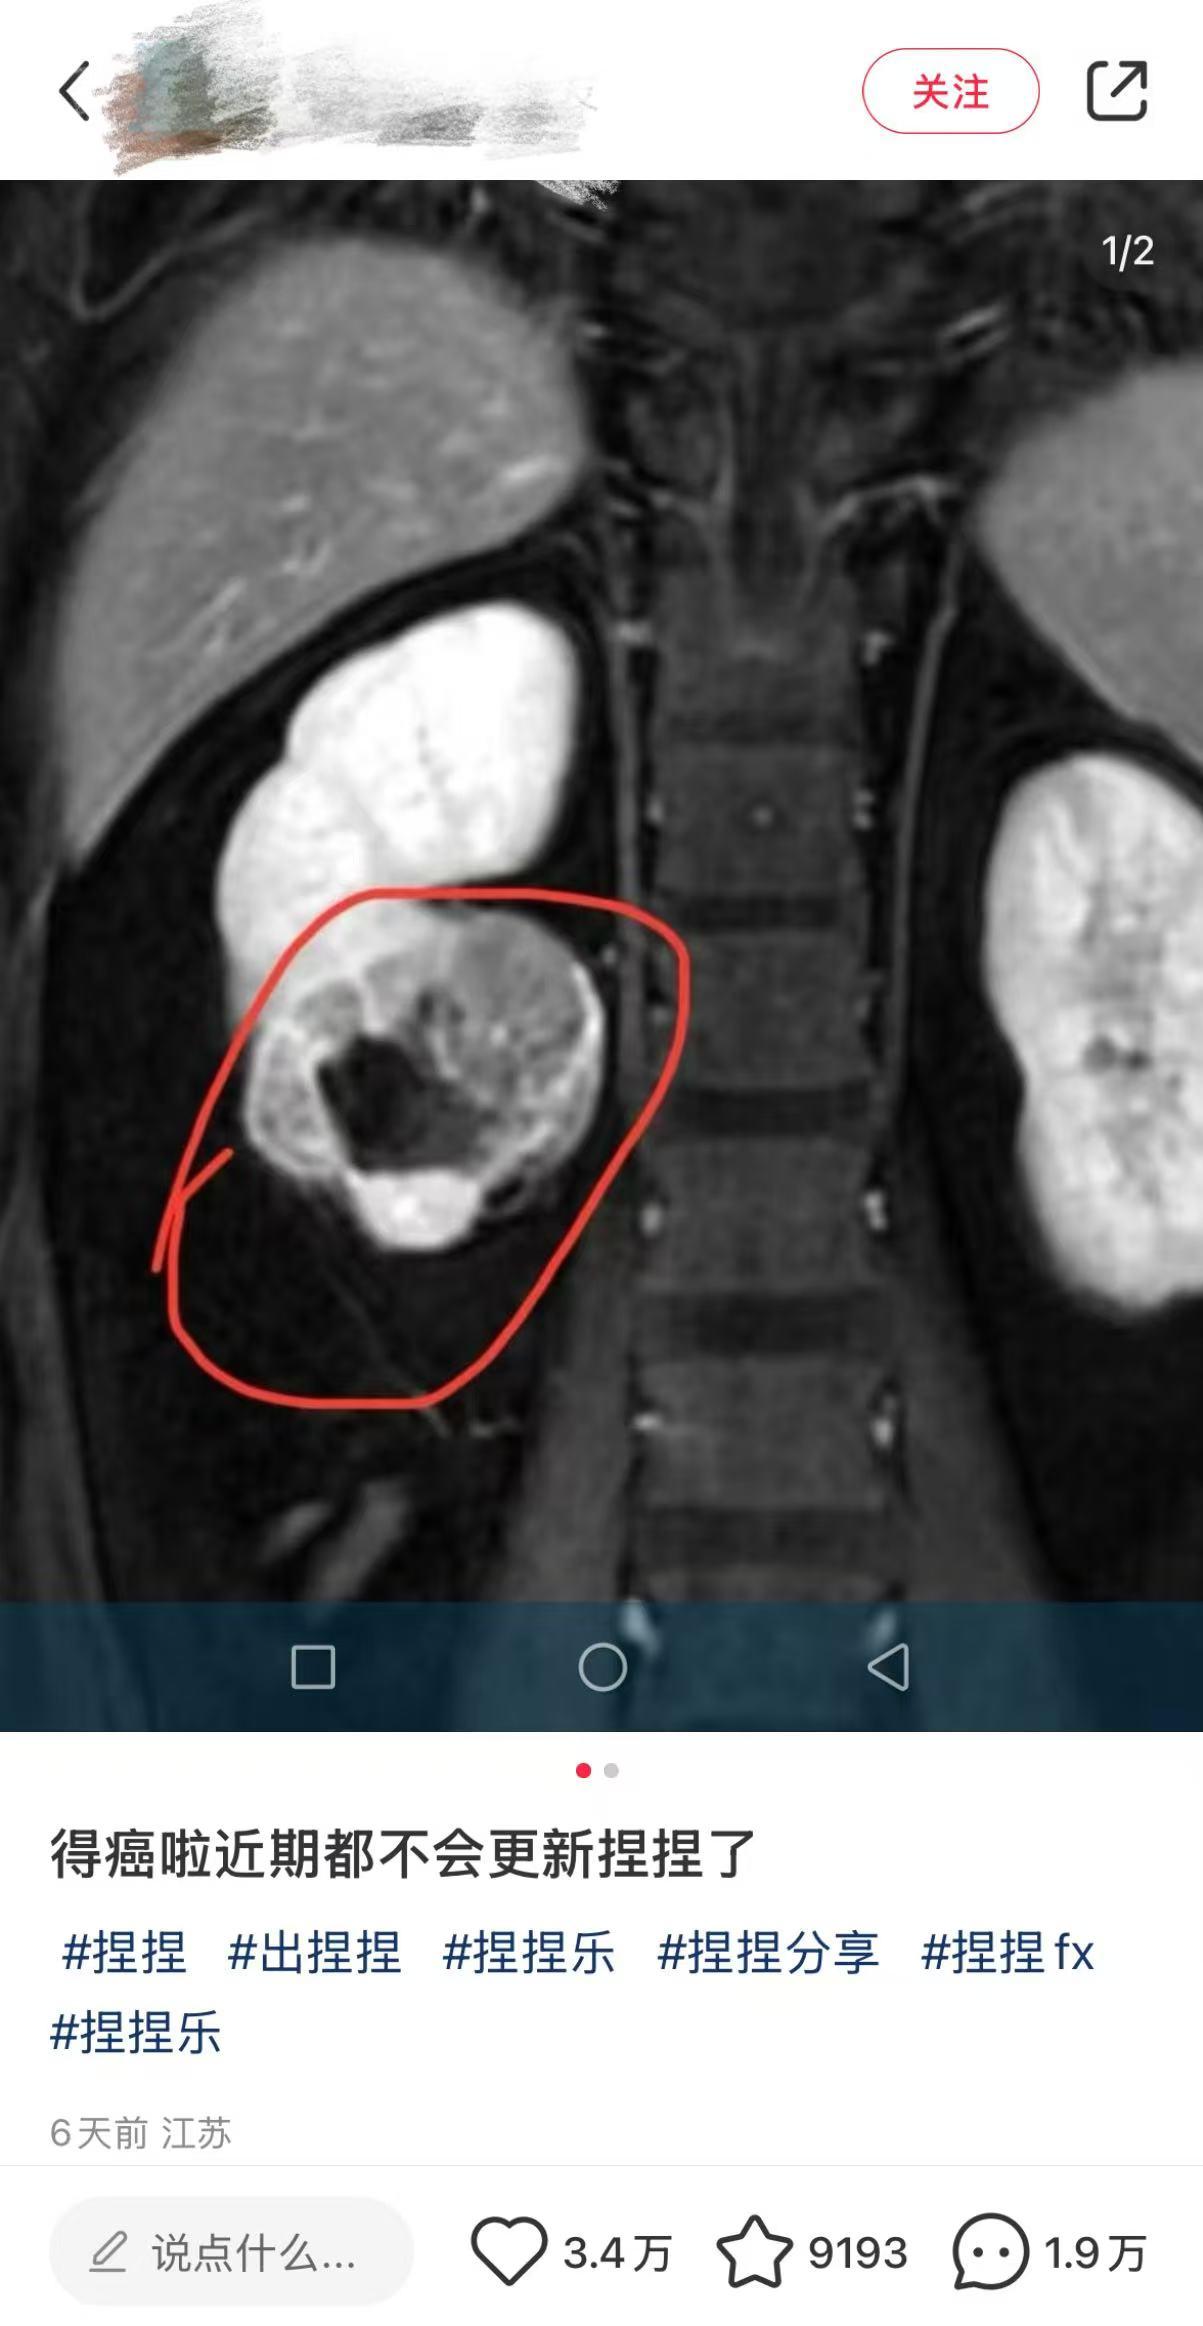

近日,一位解压“捏捏”玩具博主在个人账号上发文透露自己患癌症,并宣布将暂时停止更新与“捏捏”玩具相关的所有视频内容。尽管该博主在文案中并未明确提及具体的患癌原因,但评论区不乏猜测,其患癌原因可能与长时间接触“捏捏”玩具有关。